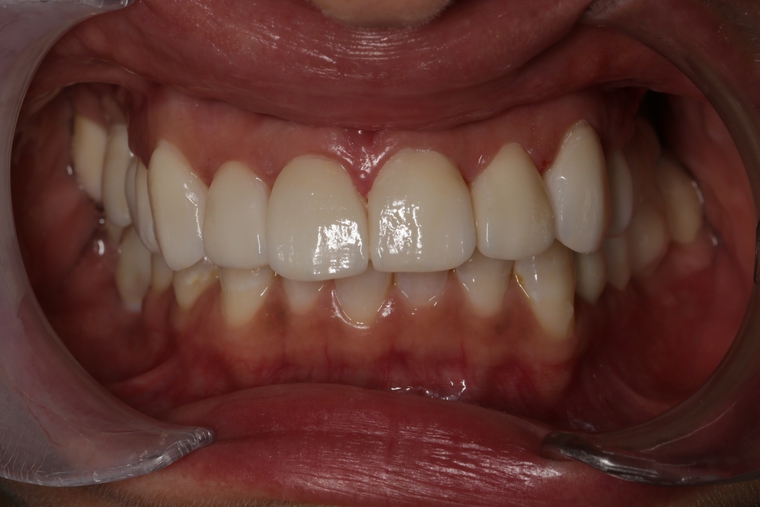

Ein Tätigkeitsschwerpunkt unserer Praxis in Salzburg ist die Implantologie. Wenn ein Zahn fehlt oder entfernt werden muss, sollte immer die Möglichkeit der Implantation im Vordergrund stehen. Ein Implantat verhält sich von den Eigenschaften genau so wie ein natürlicher Zahn. Egal ob nur ein einzelner Zahn vom Zahnarzt ersetzt werden muss oder ein ganzer Kiefer mit festsitzendem Zahnersatz versorgt werden soll, wir finden für Sie eine Möglichkeit, auch wenn die Voraussetzungen ausweglos erscheinen. Wenn möglich versorgen wir unsere Patienten mit Keramikimplantaten. Diese sind immun-neutral und können sehr oft direkt bei der Zahnextraktion eingesetzt werden. Für unsere Patienten ist daher meist nur ein operativer Eingriff notwendig!